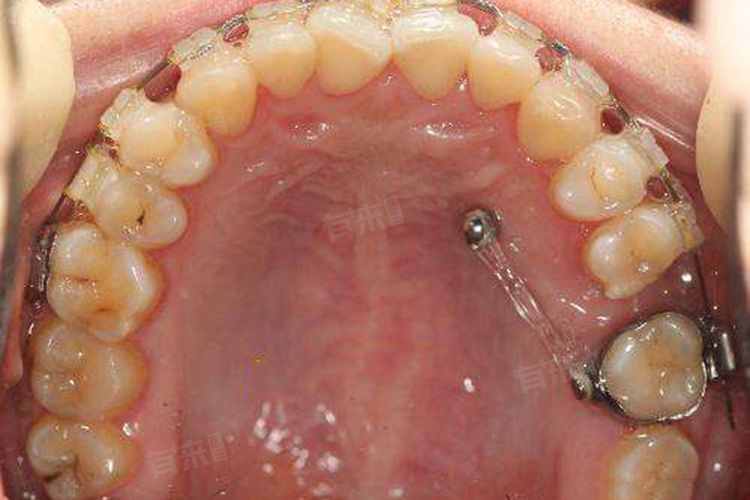

2、龅牙矫正:龅牙患者由于牙齿对外凸出,需要一个稳定的施力固定源。通过将骨钉植入牙槽骨中,可以增强后牙或前颚的支抗力,帮助突出的龅牙更好地内收,使排列不齐的牙齿受到牵引移动,从而达到矫治龅牙的目的。

3、复杂矫正情况:在处理一些复杂的牙齿矫正情况时,如牙齿前突、深覆合等,骨钉能够提供更强的支抗力,使矫正效果更加显著。通过骨钉的辅助,可以更有效地控制牙齿的移动方向和速度,缩短矫正时间。

4、辅助固定牙齿:在矫正过程中,有时需要固定某些不需要移动的牙齿,以防止其受到不必要的力而移位。骨钉可以作为一个稳定的支点,帮助固定这些牙齿,从而保证整体矫正效果。